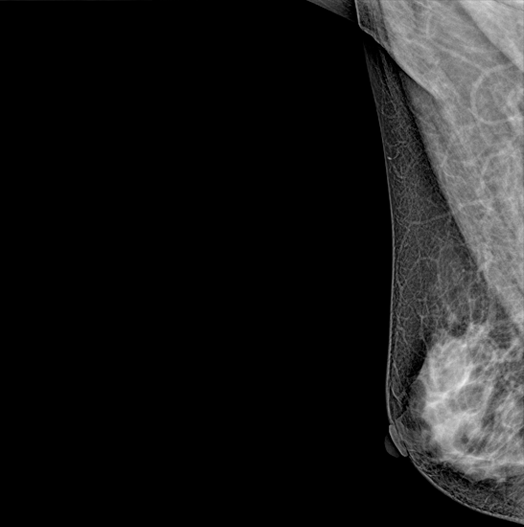

DBT (Digital Breast Tomosynthesis)

The X-ray tube moves on the breast and takes high-definition, high-resolution images with high contrast from various angles.

The images are reconstructed in 3D TO Provide accurate information about the location and condition of the lesion